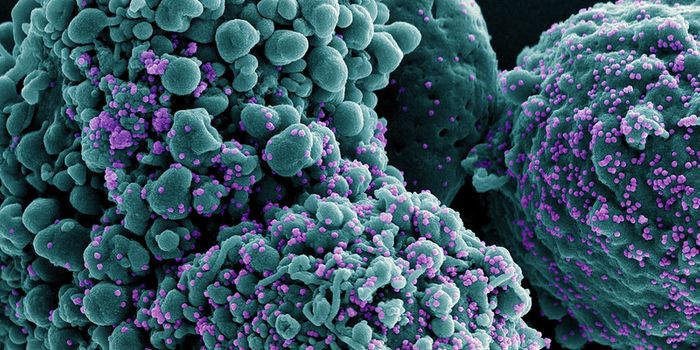

SEP 08, 2024MicrobiologySARS-CoV-2, the pandemic virus that causes COVID-19, has mutated endlessly since it burst on the scene in late 2019. An ...

AUG 27, 2024MicrobiologySince the start of the COVID-19 pandemic, the virus that causes the illness - SARS-CoV-2 - has had a practically infinit ...